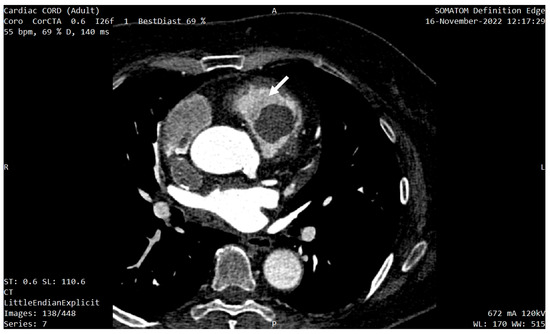

In order to better characterize the tumor, the investigations were completed with a cardiac CT and a cardiac MRI (CMR). The CT described a 33/26/23 mm hypodense, oval-shaped, slightly lobulated, well-circumscribed mass located 3 mm anterior of the pulmonary valve, which occupied 80% of the RVOT and was in contact with the medial and anterior wall of the RV (Figure 4 and Figure 5a,b). No coronary artery lesions were found.

Figure 4. Cardiac CT showing the mass localization 3 mm anterior of the pulmonary valve (white arrow), occupying 80% of the RVOT.